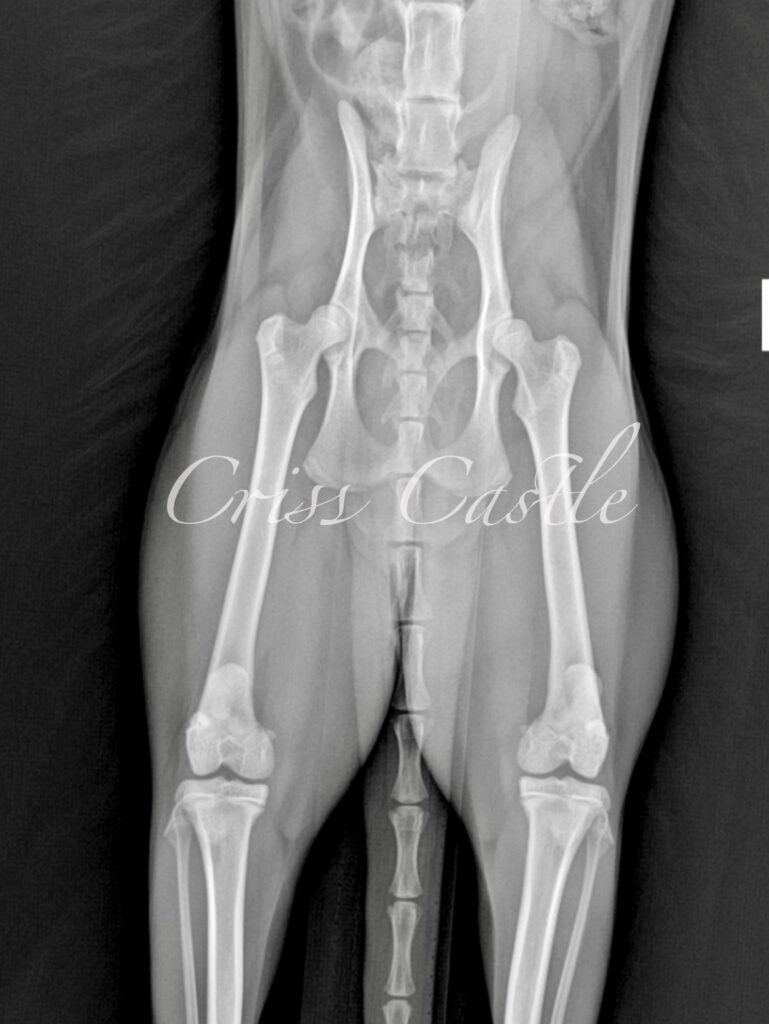

Below are the current hip x-ray results for each Criss Castle breeding cat.

Note that as the cats continue to grow, this page may be updated with new results.